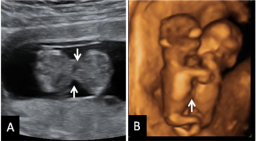

Ecografía de la semana 12

Confirma la edad gestacional y el número de bebés

Los motivos por los que los ginecólogos recomiendan realizar una ecografía en la semana 12 de embarazo tienen que ver con el desarrollo anatómico y el tamaño del feto: ahora es lo bastante grande para comprobar si presenta anomalías. Además, ya se puede ver con claridad si hay uno o dos (o tres) bebés, calcular  la fecha probable de parto teniendo en cuenta la edad gestacional, y confirmar que esta coincide con el desarrollo del bebé. Se puede medir el llamado pliegue nucal (si sobrepasa unos parámetros a veces es indicio de problemas cromosómicos) y, si el bebé se deja, conocer su sexo.